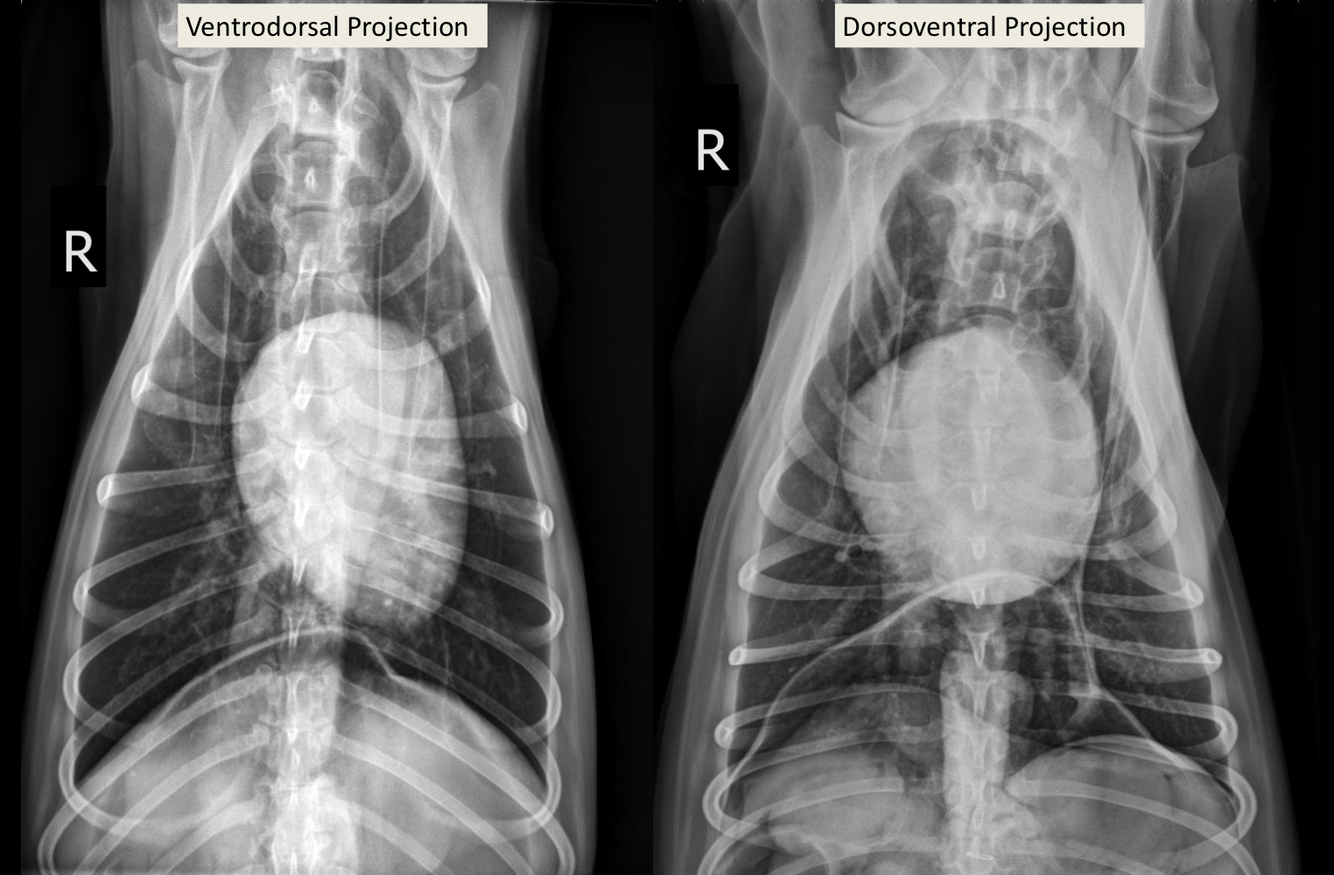

What is likely happening in this radiograph?

A

• large soft tissue mass - opacity extends into thorax

• rib lesions

• mass displaces cardiac silhouette to the left